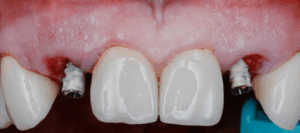

Once both temporary abutments were passively seated, the temporary shells were adjusted to be seated over the abutments freely. Sometimes some adjustment can be needed to increase the diameter of the abutment hole.

The custom shells were picked up using a self-cure composite based temporary material (Integrity), the wings can be removed at this stage and the “sub- critical zone” of the emergence profile was customized chairside by hand using a flowable composite and football diamond bur

The screw retained temporary restorations were hand tightened to about 15N and sealed with Teflon tape and Fermit™ Temporary Filling Material.

There should be no centric or protrusive occlusal contact. If the adjacent teeth are periodontally compromised, I also prefer to have very light proximal contacts to avoid any micro movement from the adjacent teeth during normal mastication